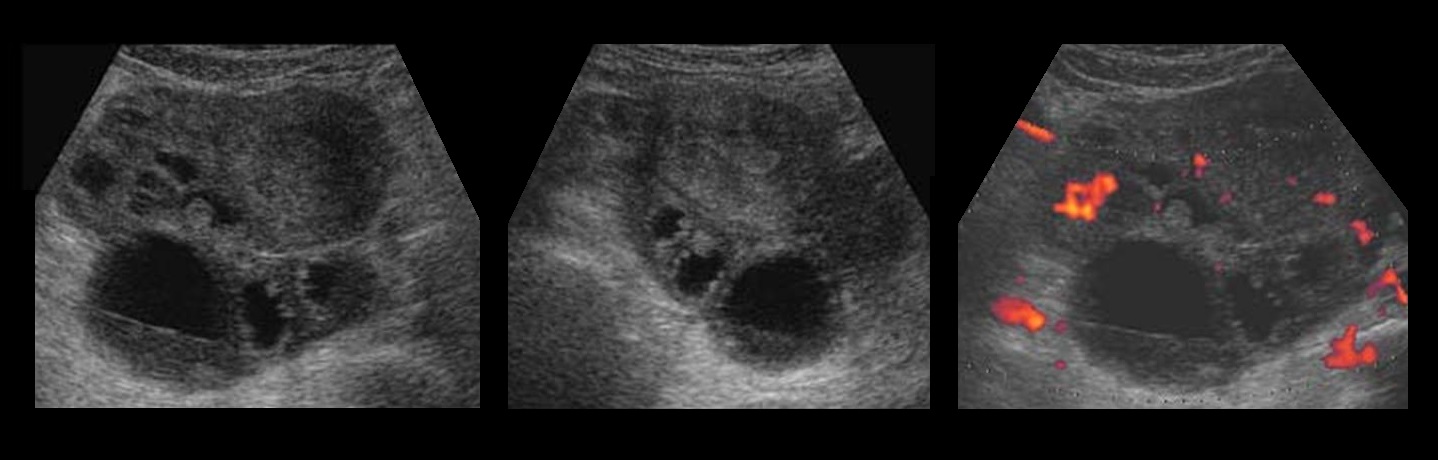

В процессе УЗИ специалист определяет расположение новообразований, а также их характеристику, формы и непосредственные размеры. Чтобы отличить доброкачественную кистому от злокачественной, врачом может проводиться специальное цветовое доплеровсое картирование. С его помощью подтверждается наличие или отсутствие кровотока в новообразовании, чем и отличается характер опухоли.

Воспаление придатков на УЗИ

Воспаление маточных труб сопровождается экссудацией жидкости в просвет — гидросальпинкс. На УЗИ между маткой и нормальным яичником определяется вытянутой формы одно- или многокамерное анэхогенное образование с тонкими стенками. При хроническом сальпингите стенка маточных труб утолщена, по периферии гиперэхогенные мелкие (2-3 мм) структуры по типу «бисера»; в просвете неоднородная взвесь.

Рисунок. Женщина с жалобами на тянущие боли внизу живота, появились нескольких дней. Матка и правый яичник удалены 4 года назад. На УЗИ левый яичник соприкасается с анэхогенной трубчатой структурой с неполными перегородками. Заключение: Гидросальпинкс слева.

Рисунок. На УЗИ между маткой и яичником определяется многокамерная анэхогенная структура, стенки толстые с мелкими гиперэхогенными включениями по типу «бисера», в просвете мелкодисперсная взвесь и уровни. Заключение: Хронический сальпингит.

Кистомы яичника

– серозные и муциноз-ные эпителиальные доброкачественные опухоли. Морфологически различают гладкостенные и папиллярные кистомы. Гладкостенная серозная кистома представляет собой шаровидное одно- или многокамерное образование с тонкими стенками, содержащее светлую опалесцирующую жидкость, выстланное изнутри мерцательным эпителием. Как правило, опухоль односторонняя, небольшая, но встречаются опухоли, масса которых достигает нескольких килограммов. Папиллярная серозная кистома отличается от гладкостенной наличием сосочковых разрастаний на внутренней поверхности, а иногда и снаружи. Нередко поражаются оба яичника, возникают сращения с соседними органами, асцит. Серозные кистомы развиваются чаще в пре-и постменопаузе. Муцинозные кистомы получили свое название из-за слизеподобного содержимого. Опухоли, как правило, многокамерные, имеют дольчатую поверхность за счет выбухающих отдельных камер, могут достигать больших размеров. При папиллярных муцинозных кистомах с разрастанием сосочков на поверхности опухоли нередко возникает асцит. Муцинозные кистомы наблюдаются обычно в возрасте 40-60 лет, папиллярные опухоли – в постменопаузе.